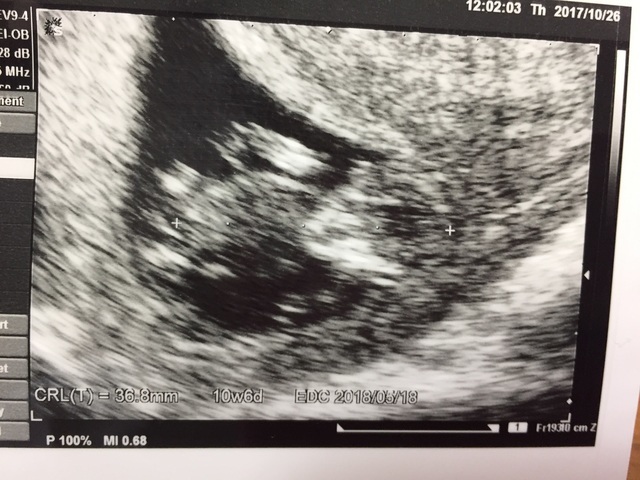

10週5日(10w5d・女の子)|響子 さん(28歳)

エコー写真撮影時のエピソード:

たくさんエコー写真をいただきましたが、この写真が最も愛らしくてお気に入りです。初めてお腹に赤ちゃんがいるんだなぁ…と実感できた写真です。クリオネみたいですが小さいながらも一生懸命に生きてくれていて感動でした。このあたりは友人の結婚式があり、不安ながらも飛行機で帰省して出席しました。悪阻はゼロに等しかったのですが、冬ということもあり坐骨神経痛が酷く長時間立ったり15分以上歩くのが辛かったです。この先どうなることやらと心配しました。結局暖かくなるにつれ腰痛は治り出産前日もバリバリ動かことができました。